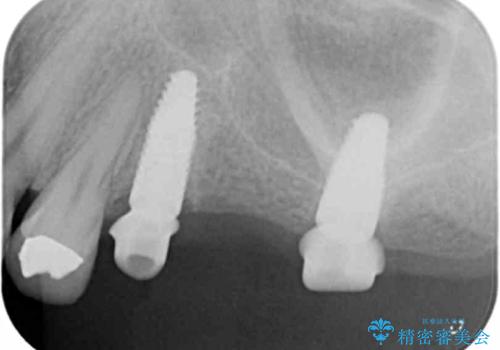

- 奥歯に入れていたブリッジがダメになり歯を抜去、全然噛めなくなった、インプラント治療を受けたい!と奥歯の機能回復を希望され来院されました。

奥歯はすでに3本失った状態で、この状態で歯を入れるには「入れ歯」か、「インプラント」の2択となります。

- 110万円(インプラント×2・チタンカスタムアバットメント×2・ジルコニアクラウン×3・仮歯×3)費用は治療当時の料金となります